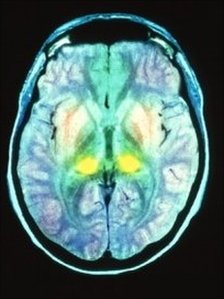

Variant Creutzfeldt-Jakob disease is a terrible legacy of the BSE outbreak. The fatal degenerative brain disorder is the human form of Bovine Spongiform Encephalopathy, commonly referred to as "mad-cow disease". It first emerged in 1995. The disease, which affects the brain, is believed to have passed from cattle to humans through consumption of meat products contaminated with BSE.

The issue gets little publicity these days, but news in The Lancet medical journal of a prototype blood test for the condition is a significant moment. Researchers at the Medical Research Council Prion Unit at University College London have managed to devise a test which can spot the infectious proteins - prions - responsible.

Prions, which cause vCJD and other fatal diseases, can inhabit a person's body for 50 years before presenting symptoms. So there has always been a suspicion that the true scale of the vCJD infection has remained hidden. A study of tonsil samples suggested that 1 in 4,000 Britons might have the disease, but no-one really knows whether that is an accurate estimate (opens pdf). One positive fact is that the number of deaths from vCJD has been falling steadily since a peak of 28 in 2000.